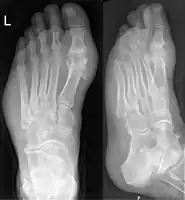

- Gout on X-rays of a left foot in the metatarsal-phalangeal joint of the big toe. Note also the soft tissue swelling at the lateral border of the foot.